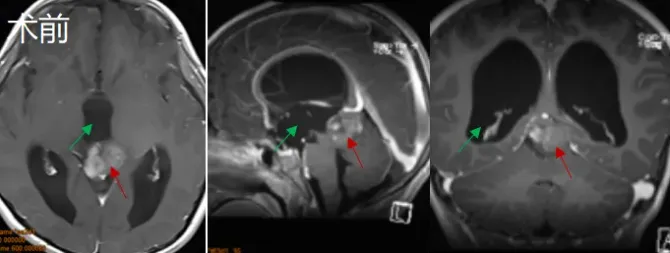

术前情况

8岁患儿晃晃因恶心呕吐、头晕等症状就诊,检查发现松果体区肿瘤,伴有幕上梗阻性脑积水。多位专家建议行脑脊液分流术辅以放疗和化疗。然而,巴特朗菲教授评估晃晃病情后指出,患儿目前已具备手术指征,可为其施行肿瘤全切手术。

术中操作

患儿取俯卧位,采用后正中头皮切口,选择幕下小脑上入路结合幕上枕下乙状窦旁经小脑幕入路,最终成功实现肿瘤全切。